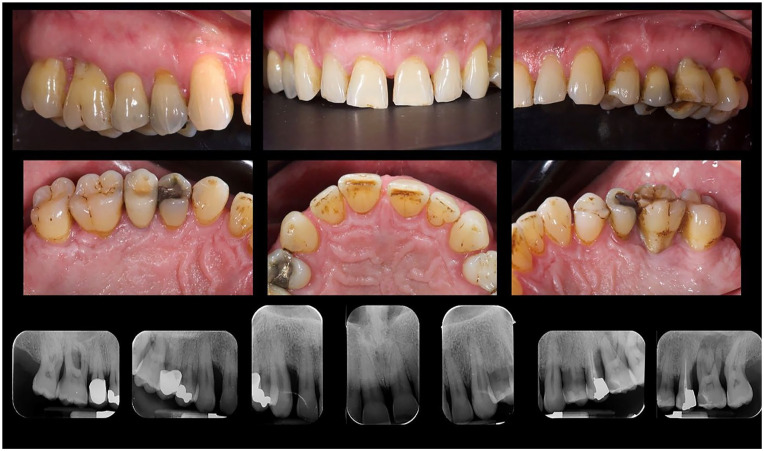

年龄相关性黄斑变性(AMD)是50岁及以上人群视力受损的主要原因,主要影响中央视力。本研究旨在调查牙周病与年龄相关性黄斑病变之间的潜在关联。66岁男性受试者,患有年龄相关性退行性黄斑病变和严重牙周病,评估和治疗。在最初阶段的非手术牙周治疗后,重新评估牙周指标。此外,还进行了用种植体代替无希望牙的拔牙。视网膜地形图用于评估可能的病理消退,并给予适当的抗vegf治疗。结果显示牙周病的消退和退行性黄斑病变的改善。这些初步结果即使令人鼓舞,也应该得到更大规模前瞻性试验的支持。

Age-related macular degeneration (AMD) is a leading cause of significant vision impairment in individuals aged 50 and older, primarily impacting central vision. This study seeks to investigate potential associations between periodontal disease and age-related maculopathy in the analyzed clinical case. A male subject of 66 years old, with age-related degenerative maculopathy and severe periodontal disease, was evaluated and treated. After an initial phase of non-surgical causal periodontal therapy, the periodontal indices were re-evaluated. In addition, the extraction of hopeless teeth replaced by dental implants was performed. A retinal topography was used to assess possible regression of the pathology, and proper anti-VEGF therapy was administered. The results showed a regression of periodontal disease and an improvement of the degenerative maculopathy. These preliminary results, even if encouraging, should be supported by larger prospective trials.